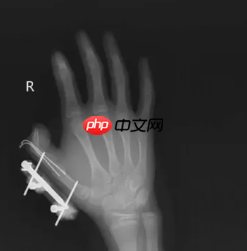

结果密封袋里的干冰突然爆炸,小朋友的右手瞬间鲜血直流,拇指虎口处被撕开一道约 10 厘米的伤口,拇指骨折。

图片来源于网络